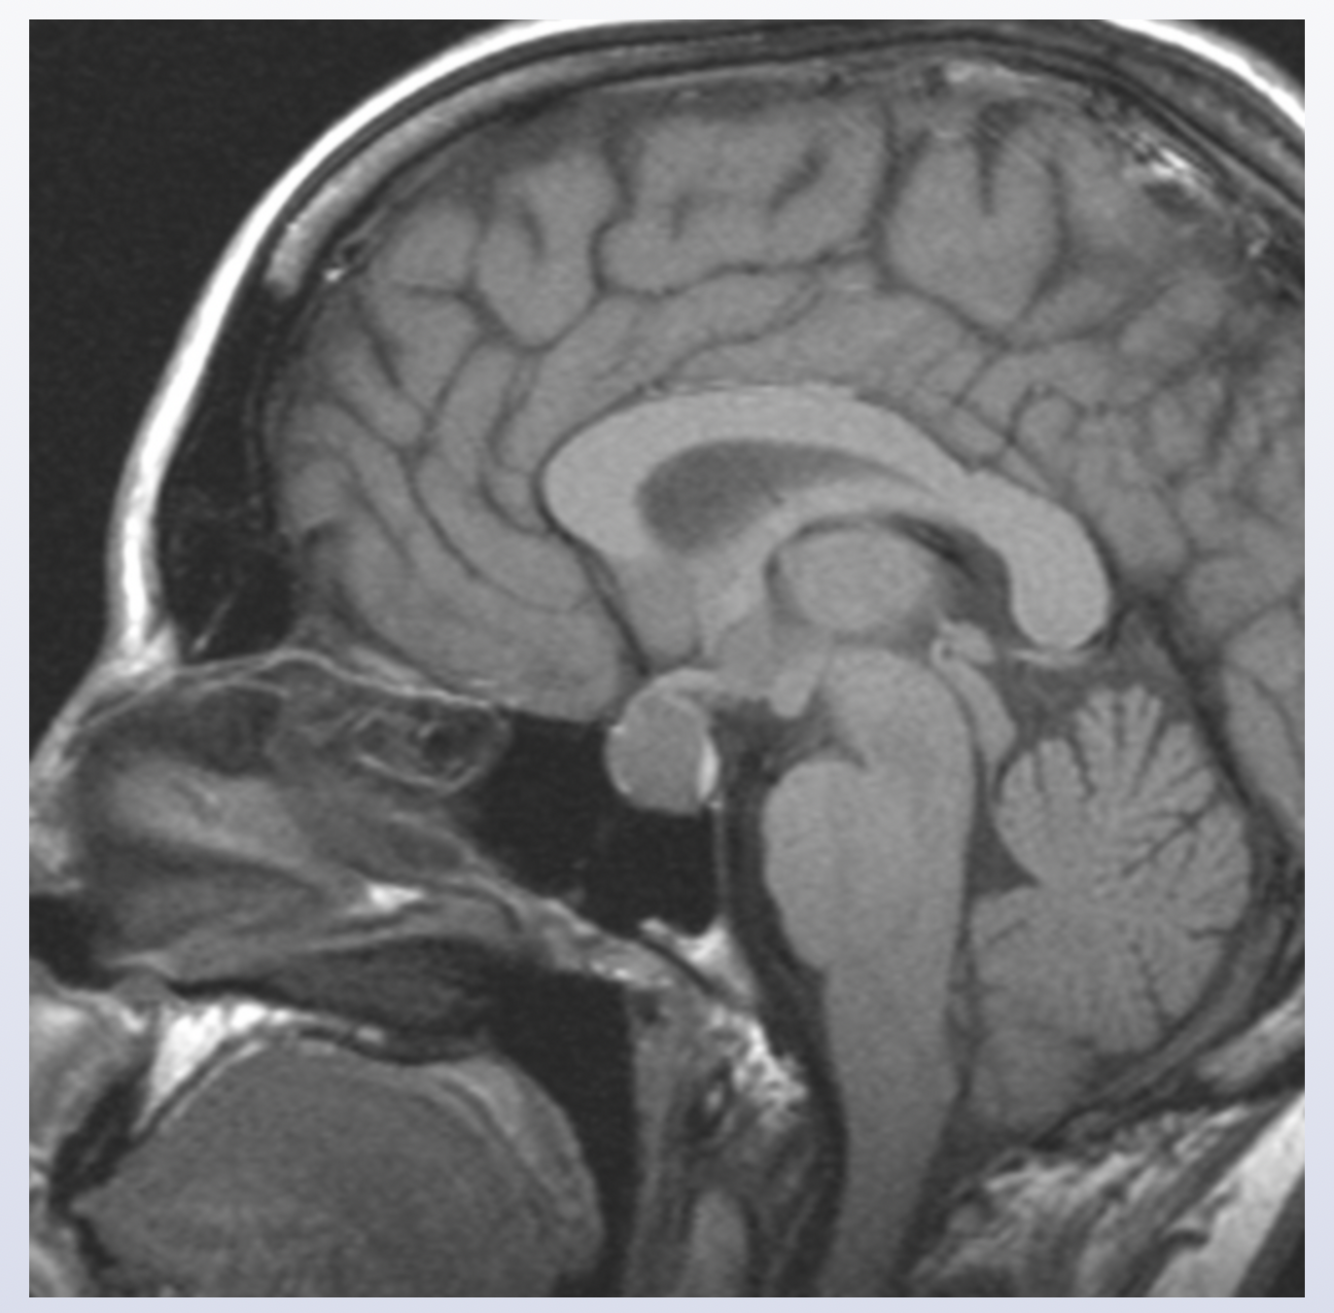

Pontine glioma

the nuclei of the vestibulococchlear nerve (CN VIII) are located in the pons; CN VIII conveys information about head position and movement and helps to stabilize the gaze during head movement; damage can lead to nystagmus